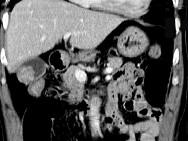

问题 男,45岁,右季肋区疼痛,Murphy征阳性,B超提示胆囊息肉,CT所见如图,最可能的诊断是()

选项 A.胆囊息肉 B.胆囊癌 C.慢性胆囊炎 D.胆囊转移癌 E.胆囊腺肌增生症

答案 B